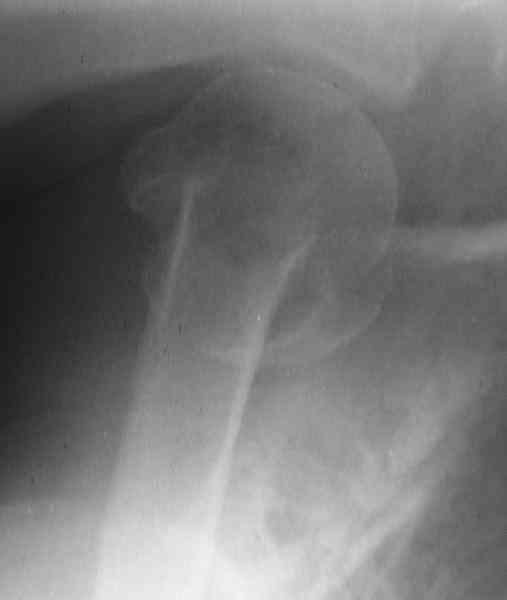

[Ortho] Comminuted fracture proximal humerus

CT scans would be useful to evaluate the head.

Another option could be closed nailing, see an example, the surgery was

done 2 days ago. In common such surgeries are performed under regional

anesthesia, not general.

Fragments now look severely displaced.